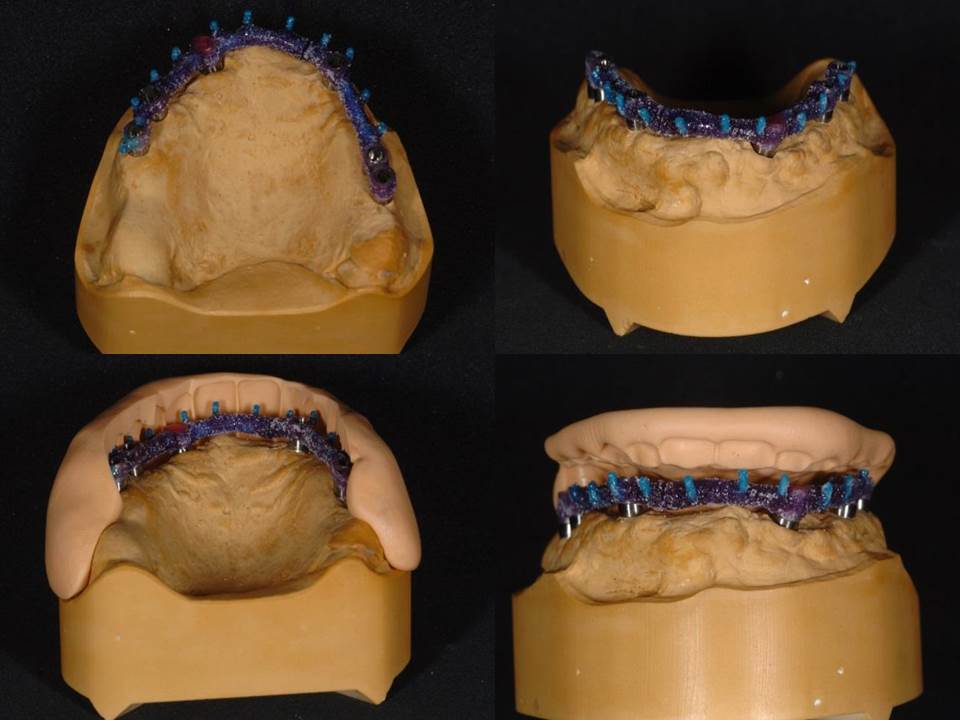

Prótesis fija OT BRIDGE

OT Equator Biologic Abutment